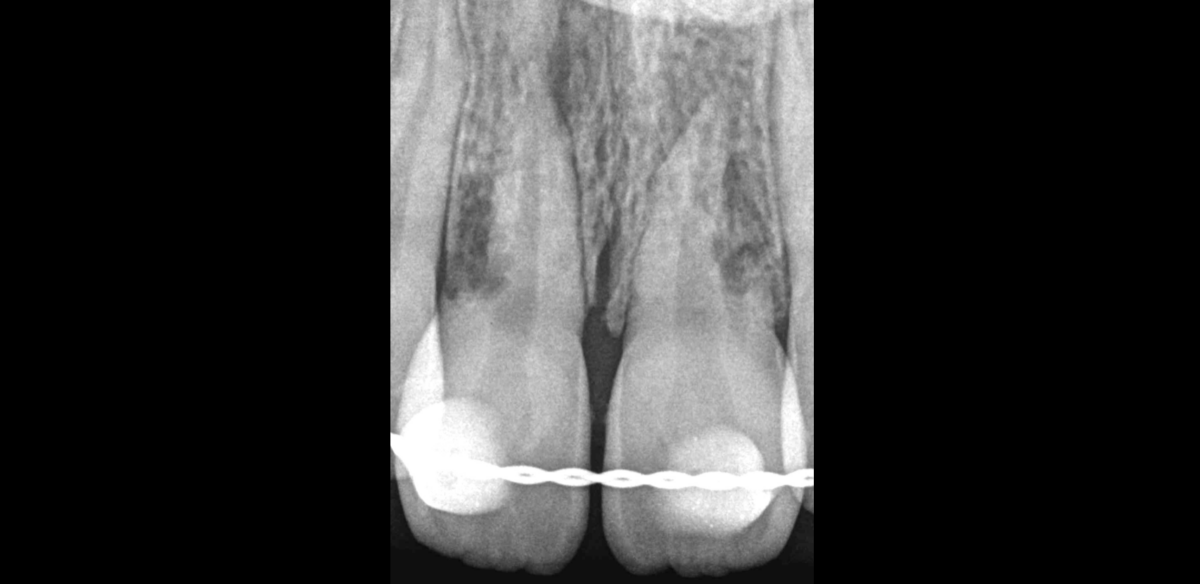

🔍 11 21

ATCD de traumatisme dentaire

Pulpe nécrosée, parodontite apicale symptomatique

Résorption latéro-radiculaire externe, inflammatoire

➡️ 𝐋𝐞 𝐩𝐫𝐨𝐧𝐨𝐬𝐭𝐢𝐜 𝐞𝐧𝐝𝐨𝐝𝐨𝐧𝐭𝐢𝐪𝐮𝐞 𝐞𝐬𝐭 𝐛𝐨𝐧 ! 𝐄𝐧𝐯𝐢𝐫𝐨𝐧 𝟖𝟎 𝐚̀ 𝟖𝟓% 𝐝𝐞 𝐜𝐡𝐚𝐧𝐜𝐞 𝐪𝐮𝐞 𝐥𝐞 𝐭𝐫𝐚𝐢𝐭𝐞𝐦𝐞𝐧𝐭 𝐬𝐨𝐢𝐭 𝐞𝐟𝐟𝐢𝐜𝐚𝐜𝐞 𝐝𝐮 𝐩𝐨𝐢𝐧𝐭 𝐝𝐞 𝐯𝐮𝐞 𝐝𝐞 𝐥𝐚 𝐜𝐢𝐜𝐚𝐭𝐫𝐢𝐬𝐚𝐭𝐢𝐨𝐧 𝐨𝐬𝐬𝐞𝐮𝐬𝐞 𝐩𝐞́𝐫𝐢 𝐚𝐩𝐢𝐜𝐚𝐥𝐞.

⚠️ C’est le facteur biomécanique (risque de fracture) qui pourrait ici devenir limitant un jour, dans le choix de conserver cette dent ou pas.